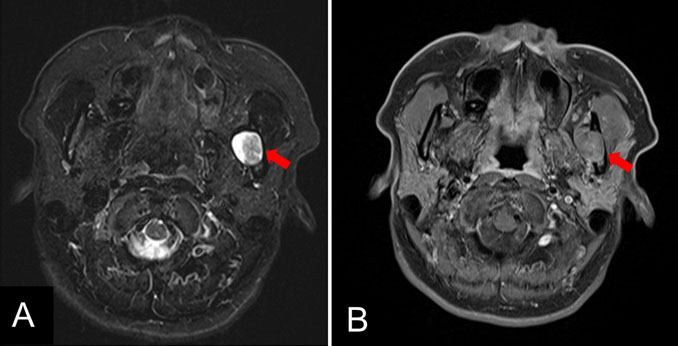

In August 2017, a 48-year-old Japanese woman visited the dental clinic because of occlusal pain in her left wisdom tooth. A panoramic X-ray showed an oval-shaped radiolucent area in the left mandibular ramus. She presented to our department for careful examination. Regarding the extraoral findings, no mass was palpable in the left mandible, and there was no dysesthesia in the left mental nerve area. Intraorally, no swelling or induration was observed inside the mandibular ramus, moreover, there was no difference between the two sides and the mucosa was a normal color. Her medical history included hyperlipidemia, iron-deficiency anemia, and diabetes. A panoramic X-ray revealed an almost circular and well-defined translucent image in the left mandibular ramus (Figure 1). Computed tomography (CT) revealed bone depression in the left mandibular ramus, and more thinning bone was seen inside. There was no obvious abnormal bone destruction. The internal density was similar to that of adipose tissue (Figure 2). Magnetic resonance imaging (MRI) revealed a lesion measuring 18×17×21 mm in size with mixed moderate and high signal intensity on fat-suppressed T2-weighted imaging in the left mandibular ramus. Gadolinium contrast-enhanced T1-weighted imaging showed no clear enhancement. Based on the clinical and imaging findings, it was likely to be a cystic lesion (Figure 3). Considering the anatomical site (it was located inside the mandibular ramus), we decided not to perform biopsy.

Figure 3: Magnetic resonance imaging. (A) Gadolinium contrast-enhancedT1-weighted imaging (axial plane). (B) T2-weighted short inversion time inversion-recovery (STIR) imaging (axial plane). The T1-weighted image shows heterogenous intensity and no clear enhancement (arrow). The T2-weighted image shows mixed moderate and high signal intensity (arrow).